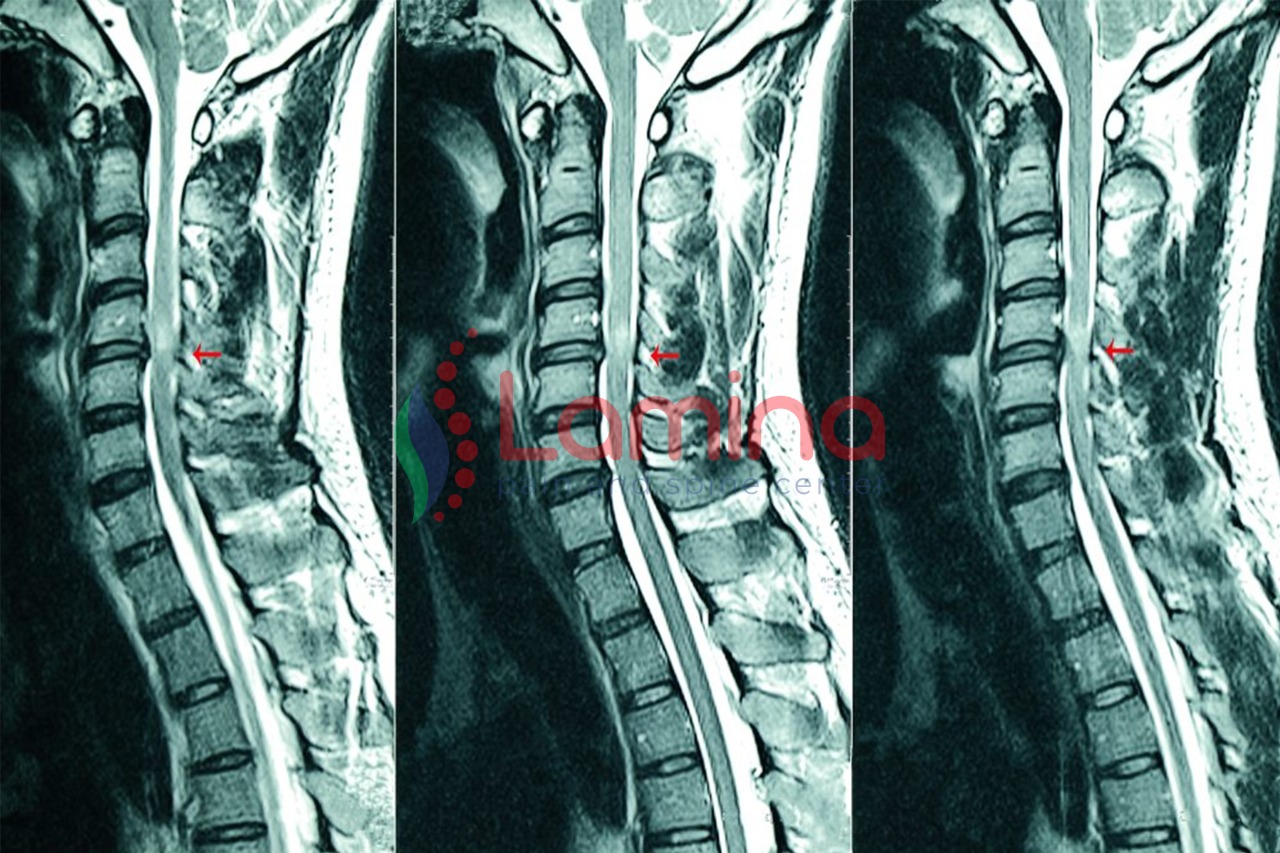

Selain pemeriksaan fisik secara langsung, dokter akan meminta Anda untuk melakukan pemeriksaan penunjang radiologis, seperti MRI untuk memastikan penyebab dan menentukan terapinya serta mengevaluasi struktur anatomi yang terganggu.

• MRI leher, melihat gambaran ruas tulang leher dengan bantalan sendi dan jaringan sekitarnya.